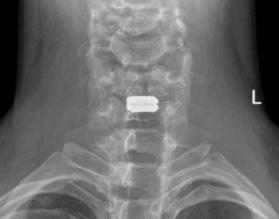

Cervical x-rays demonstrated loss of cervical lordosis with 50%-disc collapse at C5/6 with focal kyphosis. Mild scoliosis in his neck with apex at C5/6, <10 degrees.

One level ACDR, prodisc C Vivo at C5-6. Vivo was selected due to relative domed shaped at C4-5. In this case given patient’s young age and no evidence of facet arthropathy on cervical radiographs CT was not obtained. Intraoperative fluoroscopy and findings after complete discectomy and release confirmed the decision making to stick with prodisc C Vivo due to endplate morphology.